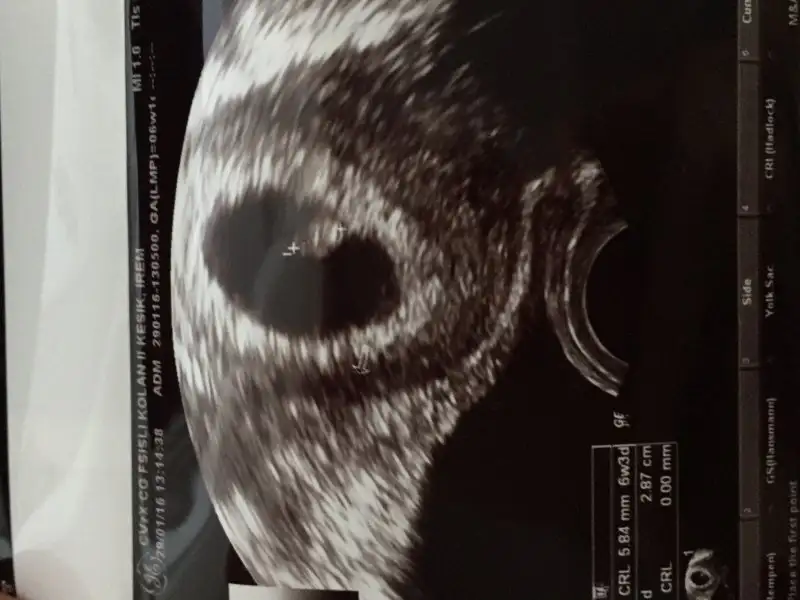

imaj ters mi düz mü yüklendi?Merhabalar benimde vajinal ultrason. 7+0 ama dr 6+1 gozukuyo gec dollenme dedi. Alabilirmiyim fikirleri

tamam düzmüş mm yazısından anladım. kız cnm ramziye göre....Merhabalar benimde vajinal ultrason. 7+0 ama dr 6+1 gozukuyo gec dollenme dedi. Alabilirmiyim fikirleri

Altta olcumu yapilanTeşekkürler hayırlısı artık :)

Cnm bu da diğer bebeğin olcumunun yapıldığı görüntü .Altta olcumu yapilan